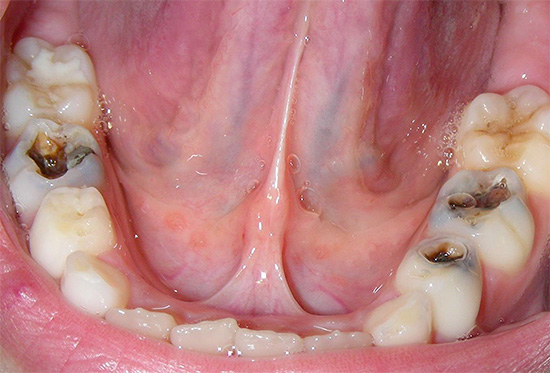

Глубокий кариес — это серьезное поражение твердой зубной ткани, которое может затрагивать дентин. Его часто путают с пульпитом, который является осложнением глубокого кариеса.

Характерной особенностью глубокого кариеса является тонкий слой дентина, который постепенно разрушается, что указывает на последнюю стадию заболевания. Это тяжелая фаза, требующая комплексного лечения и качественного вмешательства.

Глубокий кариес требует внимательного подхода к лечению. Симптомы могут включать постоянную зубную боль, особенно при контакте с горячей или холодной пищей, а также темные пятна на эмали. В некоторых случаях наблюдается отек десен и неприятный запах изо рта.

- Дефект на зубной поверхности – заметный поврежденный зуб при улыбке или разговоре заставляет человека быстрее обратиться к стоматологу. Если проблема в труднодоступной области, пациент обращается только при сильной боли, что часто указывает на пульпит.

- Неприятный запах изо рта возникает из-за активности патогенных бактерий и распада тканей пораженного зуба.

- Дискомфорт при резких температурных изменениях – употребление горячей или холодной пищи может вызвать кратковременные боли из-за отсутствия эмали на поврежденном участке.

- Болевые ощущения не всегда указывают на проблему; даже незначительная и кратковременная боль может возникнуть. Сильная боль появляется, когда глубокий кариес затрагивает нерв и переходит в пульпит.